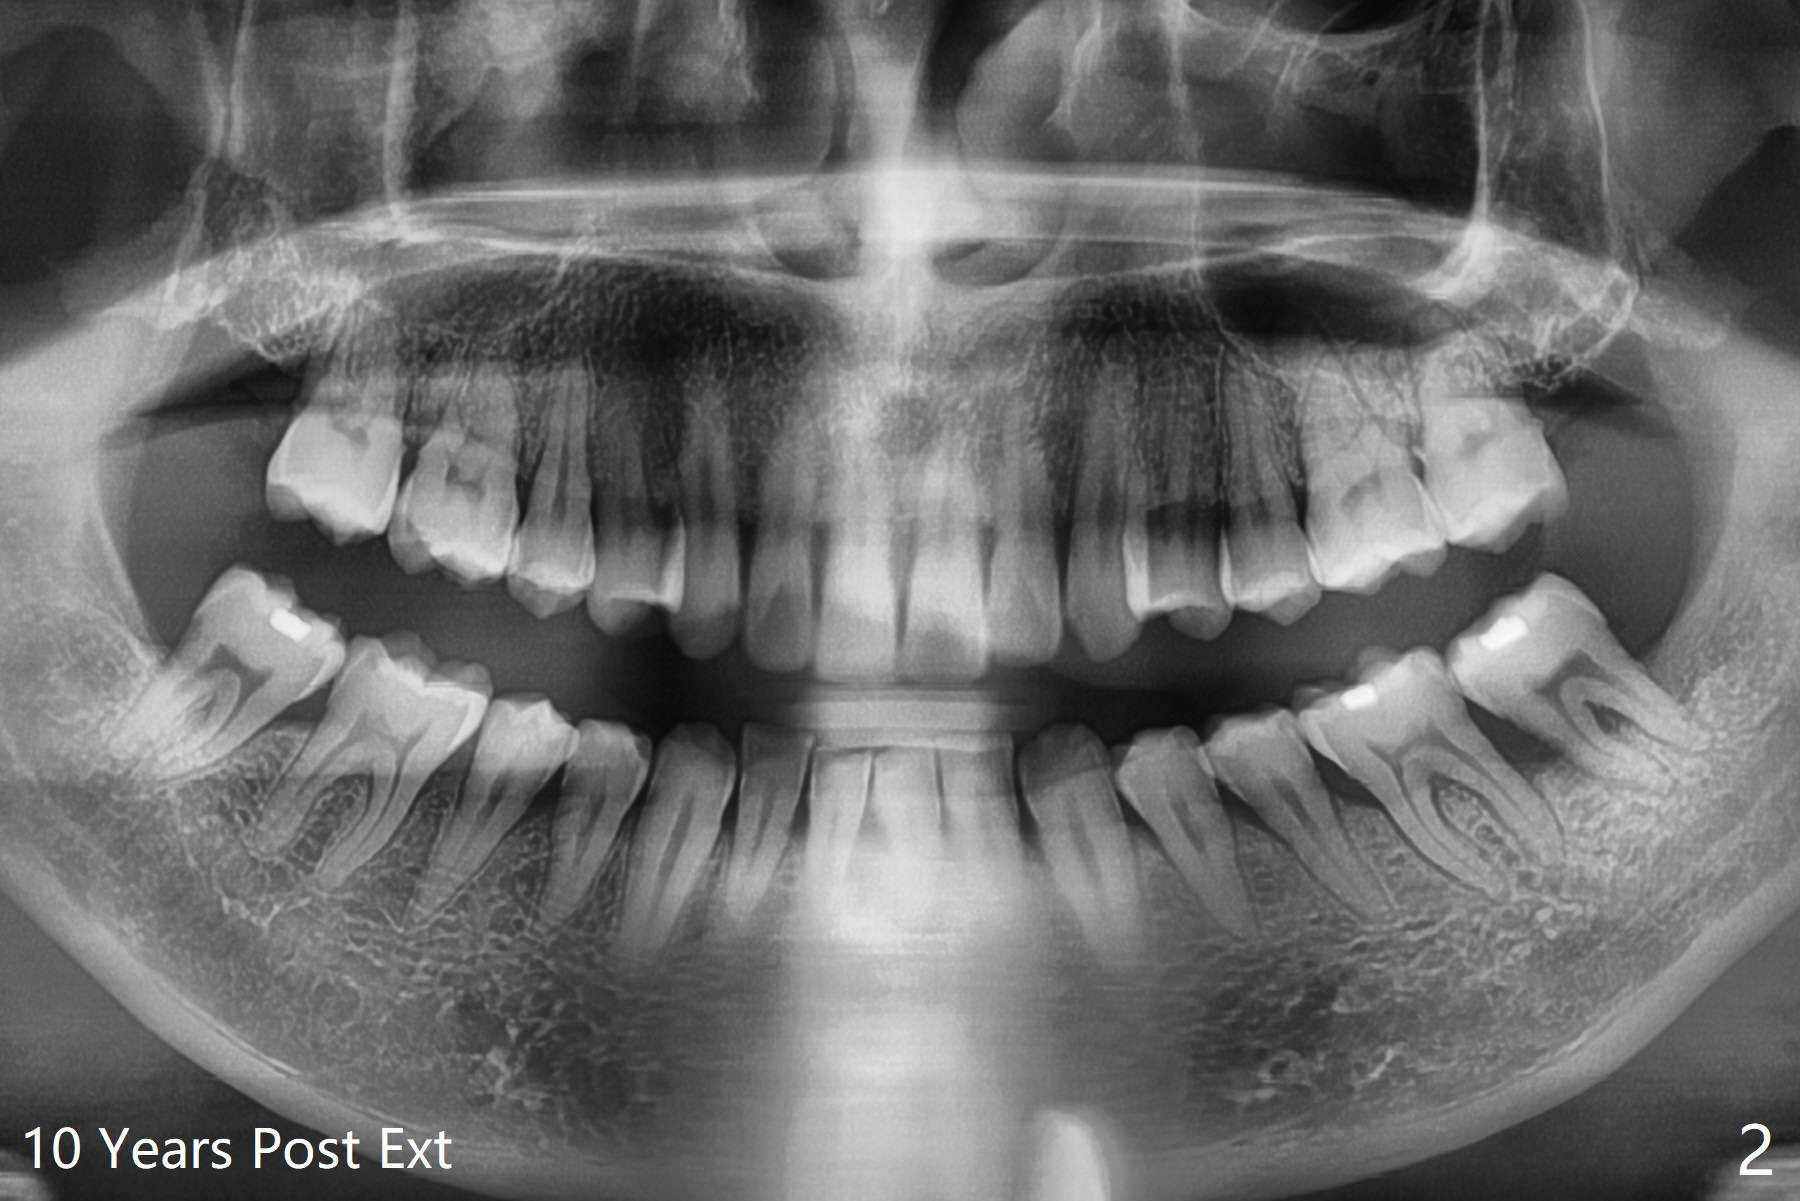

55岁男13年前就诊深洗同时拔除左下智齿(第二第三磨牙之间无骨,图一),拔除后没有植骨。十年后第二磨牙远中出现骨缺损(图二),十三年后第二磨牙松动(图三),需要拔除种植(图四)。其实当年拔除后必须植骨(图一’:红色 (白色:膜或者塞)),甚至种植(图一”:绿色),植骨。Thirteen years post #17 extraction, the lingual plate (L) is lower than the buccal one (B). Return to Prevent Molar Periimplantitis (Protocols, Table) No Caries No Antibiotic Plug 提升 手术 Xin Wei, DDS, PhD, MS 1st edition 03/27/2021, last revision 05/31/2021